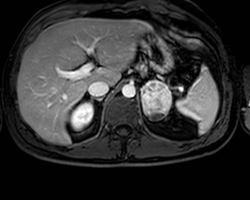

Tumeur des glandes surrénales

11 novembre 2017 308. Tumeurs du rein

• Image radiologique